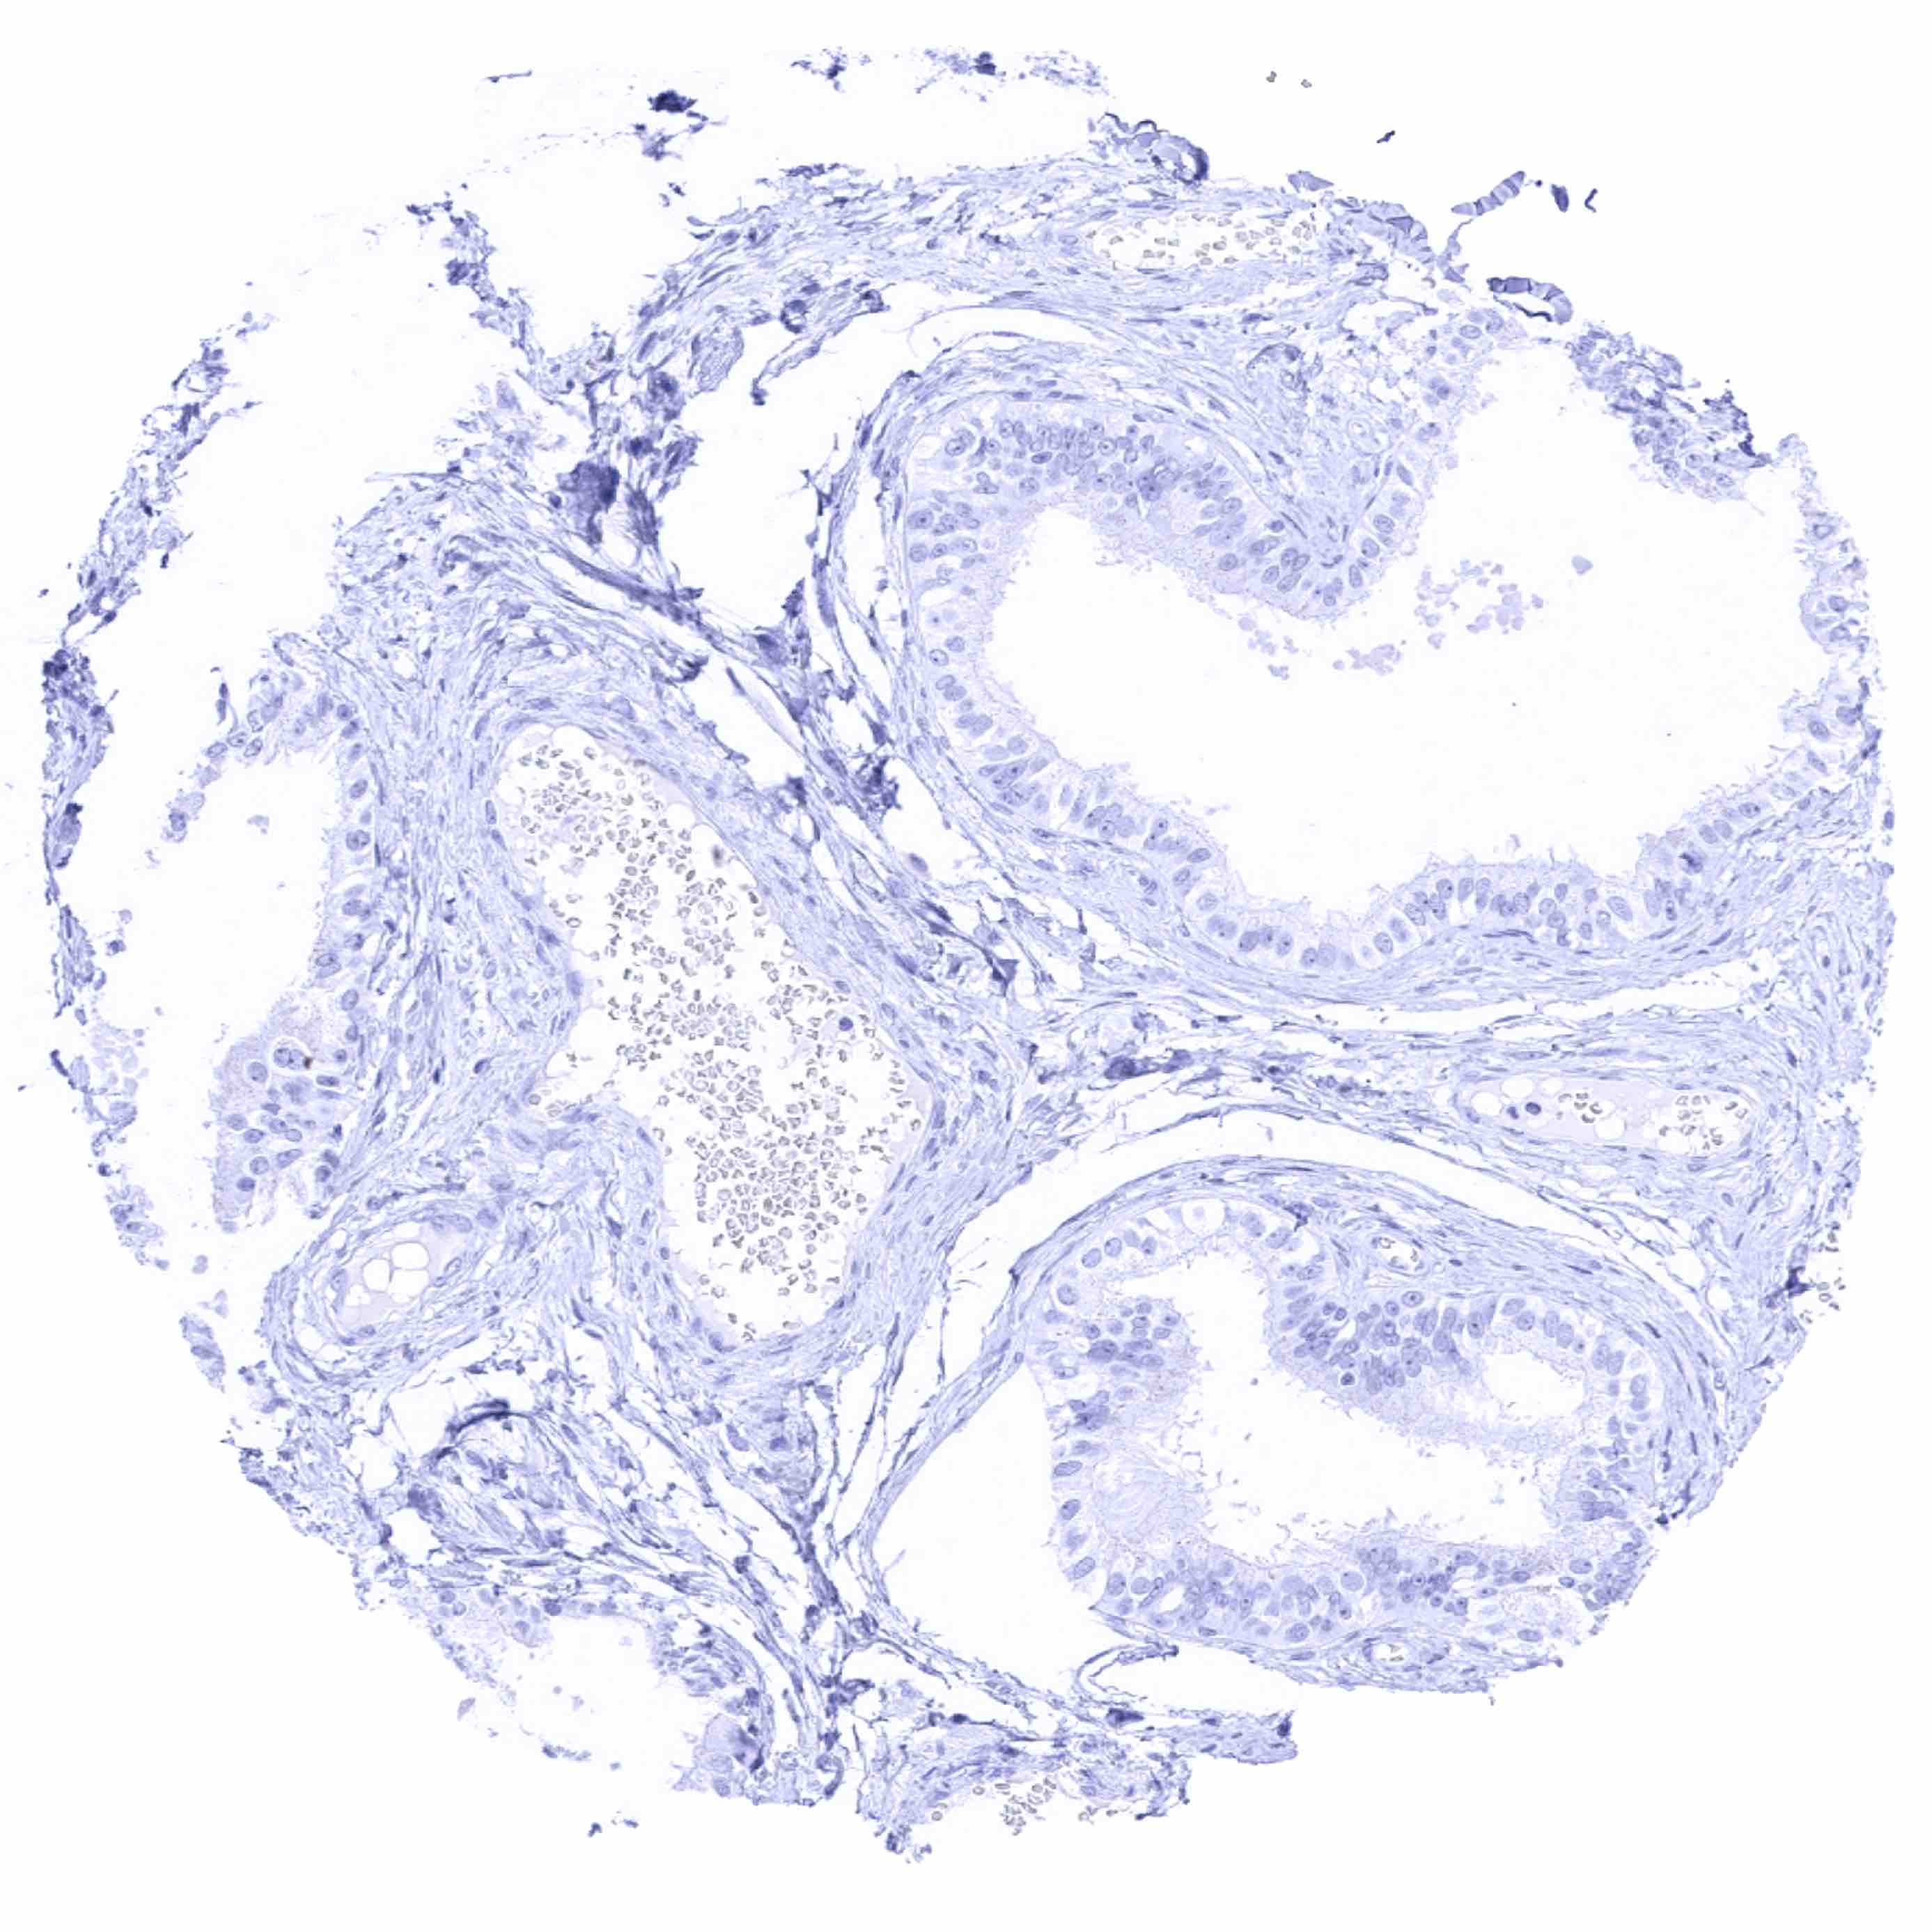

Fallopian tube, mucosa